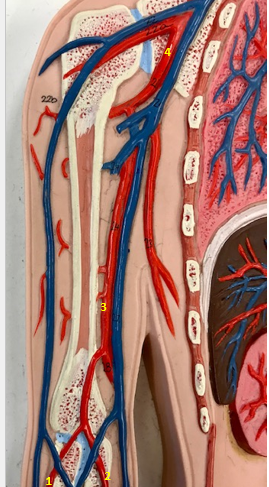

Tunica intima

Name the blue arrow

Lines lumen and release vasoactive chemicals

Function of tunica intima

Venous valves

Name the pink arrow

Prevent backflow of blood

Function of venous valves

Tunica media

Name green arrow

Vasoconstriction and vasodilation

Function of tunica media

Tunica externa

Name the purple arrow

Anchor and bind vessel

Function of tunica externa